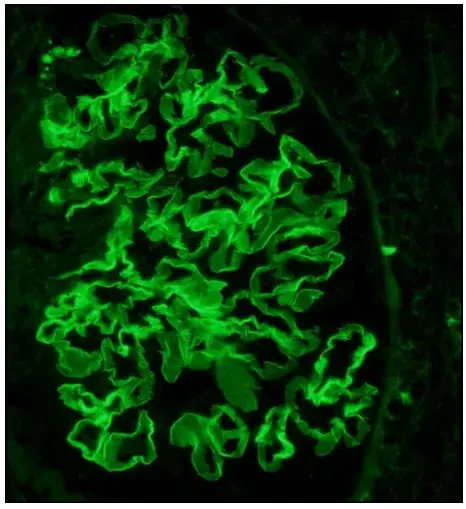

La inmunofluorescencia muestra marcação linear de IgG en la MBG (anticuerpo anti-IgG; 400×).

La inmunofluorescencia demostró un patrón de deposición lineal de IgG (policlonal), con deposición en la membrana basal glomerular (MBG), sin depósitos en la microscopía electrónica.